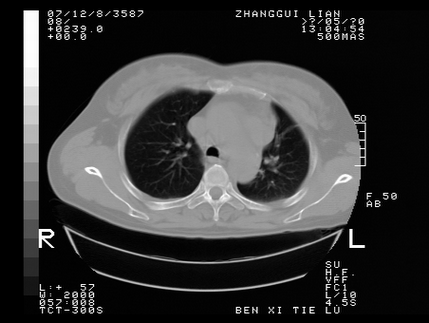

标题: CT10818:男,73,TB病史,现病史肺炎及直肠CANCER术后 [打印本页]

标题: CT10818:男,73,TB病史,现病史肺炎及直肠CANCER术后

左侧中央型肺癌伴阻塞性肺炎\\不张,左侧前上纵隔亦增宽,建议上传纵隔窗除外淋巴结转移.

考虑:左侧中央型肺癌伴阻塞性肺炎,纵隔淋巴结转移。

1)考虑为:左侧中央型肺癌伴阻塞性肺炎,纵隔淋巴结转移。2)双侧少量胸腔积液。3)心包积液。

左侧中央型肺癌伴阻塞性肺炎,纵隔淋巴结转移。

考虑左侧中央型肺癌伴阻塞性肺炎,纵隔淋巴结转移。